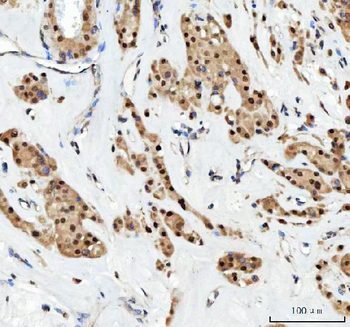

100 μl, 200 μl, 50 μlGoat anti-CYP26B1 Antibody [orb19329]

ELISA, FC, IHC

Canine, Human, Mouse, Rat

Goat

Polyclonal

Unconjugated

100 μg